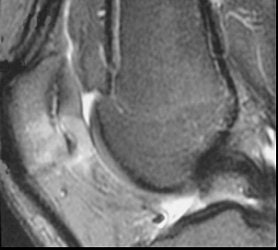

| Sagittal images of patellar tendinopathy or "jumper's knee" in a cyclist. Courtesy of Duke University Medical Center, Musculoskeletal Division, Durham, NC. |

How do cyclists get jumper's knee? "The repetitive flexion-extension process that goes around their knees can lead to strain on the patellar tendon," said Major, who sees many cycling athletes in her practice. "The tracking of that patella as it crosses the femur (causes) rubbing that can lead to problems in the joint space, and then with that tendon."